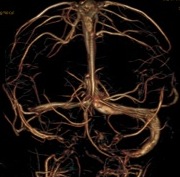

All’esame obiettivo in PS la bimba appariva abbattuta ma vigile e reattiva, presentava la tendenza alla retropulsione con impossibilità a mantenere la stazione eretta e nistagmo orizzontale a sinistra. Era inoltre presente una tumefazione del cuoio capelluto in sede occipitale sinistra, senza rime di frattura; la restante obiettività neurologica era negativa. In considerazione del quadro clinico, è stata eseguita una TC encefalo-orecchio interno che ha documentato la presenza di un’esile falda di ematoma in sede occipitale destra, associata a una iperdensità nella loggia del seno sigmoideo di destra compatibile con una trombosi del seno venoso sigmoideo.

I colleghi neurochirurghi escludevano la necessità di intervenire chirurgicamente; il completamento diagnostico mediante RM encefalo con lo studio dei seni venosi ha confermato la presenza dell’ematoma sottodurale, associato a un segnale di flusso disuniforme in tutte le pesature, in particolare a carico del seno sigmoideo destro, suggestivo di impegno endoluminale (trombosi) (Figura 1).